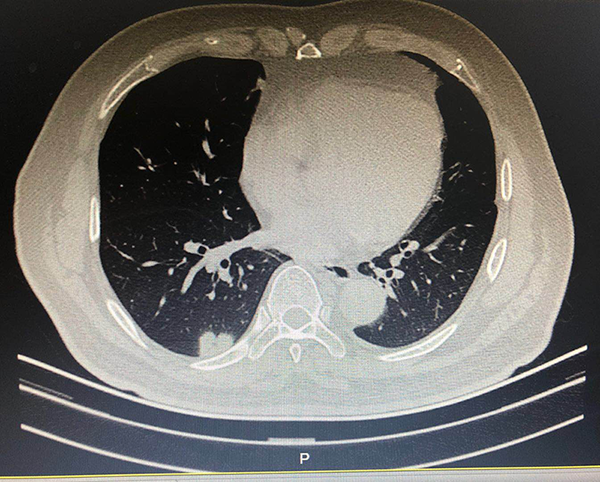

故事二、肺部磨玻璃结节别纠结

徐先生(化名)被查出肺部磨玻璃结节已有数月,且有三个——最大的约7mm,最小的5mm左右。自此,他陷入了惶惶不安,四处寻医,遍查医典,掌握了十分丰富的与肺部结节相关的医学知识。但他还是无法作出决定——开刀,或不开刀?

后经过王剑飞的一番分析与开导,徐先生终于决定手术,术后诊断——最大的是微浸润癌,其余2个是原位癌。虽然从预后看,开刀早晚差别不大,但徐先生终于安心了,又能轻松面对生活了。而对于王剑飞能想病人所想,细心考虑每一个患者的顾虑,徐先生感到十分暖心及感激。